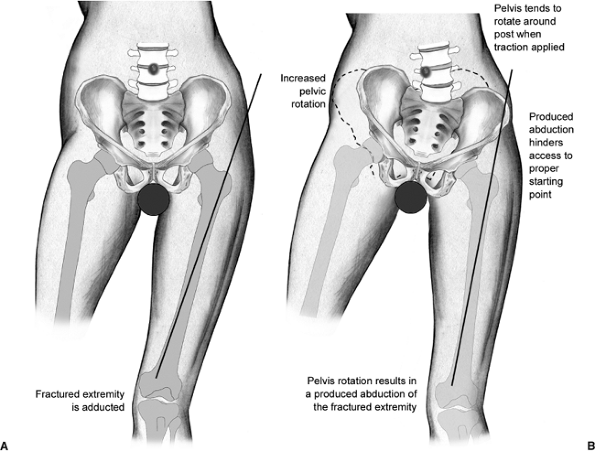

this visualization may occasionally come at a price: There is no

countertraction on the well leg. As a result, when strong traction is

applied to the fracture, the pelvis has a tendency to rotate around the

perineal post. This produces abduction of the operative side and can

significantly hamper achieving the correct starting point, leading to a

varus reduction (Fig. 17.2).